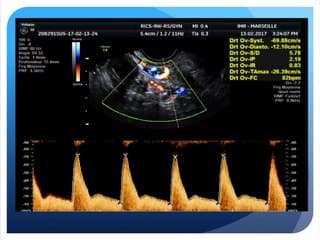

RETOUR VEINEUX CAVE: L'oreillette droite reçoit les deux veines caves: inférieure (VCI) et supérieure (VCS): arrivent verticalement du bas et du haut du foetus.Coupe bicave: partir du plan de visualisation du déroulement de la crosse de l'aorte, sur une coupe para-sagittale gauche , tangentiellement au rachis foetal, puis faire glisser la sonde de l'autre côté du rachis en para-sagittal droit, légère rotation de la sonde dans le sens horaire pour repérer les 2 veines caves arrivant dans l'oreillette droite.Si la position foetale ne le permet pas: repérer en deux temps:- VCS à partir de la coupe des 3 vaisseaux.- VCI en avant de l'aorte descendante dans le plan de coupe de la crosse de l'aorte en inclinant un peu la sonde.RETOURS VEINEUX PULMONAIRES: Accessibles à partir de la coupe des 4 cavités.Oreillette gauche: aspect en cornes de taureau au niveau de l'abouchement des veines pulmonaires.Oreillette droite: aspect arrondi.Les veines pulmonaires arrivent à plein canal dans l'oreillette droite: s'affrontent de chaque côté des la face postérieure de l'oreillette gauche.Doppler couleur: permet de visualiser l'arrivée à plein canal du flux pulmonaire dans l'oreillette gauche, se poursuivant vers l'orifice mitral.Bien regarder le sens du flux: ascendant ou descendant.